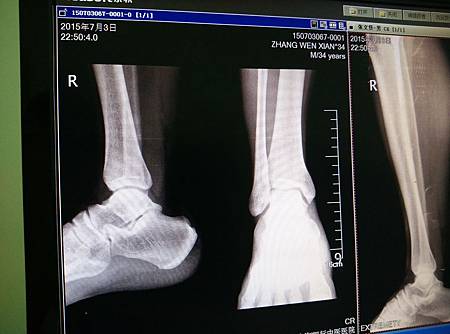

從2000開始打,就在2130上場時,

接球的一個轉身動作時,

聽到了「趴」的一聲,我就倒地了。

開始我還以為是被人撞到還是被球丟到,

後來朋友說是我自己摔的。

所以是我先聽到趴的一聲,接著自己就摔倒了。

以為沒啥大礙,走到場邊休息,

但慢慢感覺不太對勁,

感覺我是托著腳底板在走路,

又不是扭到腳,說痛也不太痛,

還好球隊上有專業的中醫師跟我說,

有可能是肌鍵斷了,建議我要去拍X光片,

不然可能很嚴重。

為了保險起見,我還是去醫院拍了X光片。

結果沒想到,還真的是肌鍵斷了,

好像就是大家常說的阿基裡斯鍵斷了,